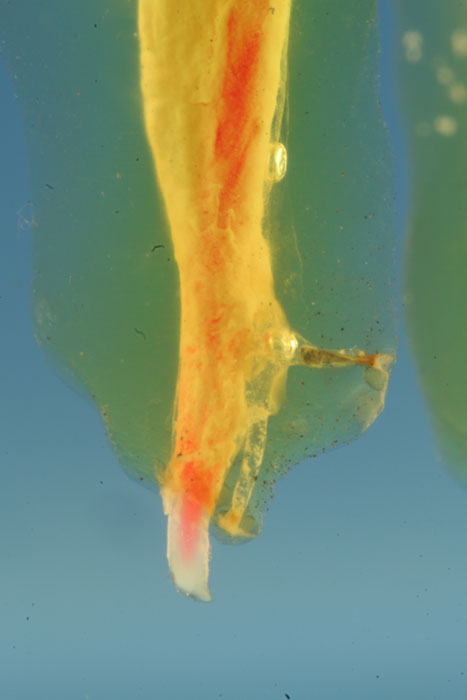

In den zwei Ansichten des transparenten Präparats ist die Verteilung von

Sealer und Guttapercha gut erkennbar.

Detailaufnahmen: die Spitze einer frakturierten Feile liegt in einem

rechtwinklig abzweigenden Seitenkanal der distalen Wurzel, andere

Ramifikationen sind nicht gefüllt.

Dass die Guttapercha aus dem distalen Foramen ragt, ist ein Artefakt der

Präparatherstellung.